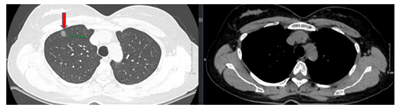

Case lâm sàng: Ứng dụng trí tuệ nhân tạo (Artificial intelligence – AI) trong chẩn đoán và điều trị sớm Ung thư phổi tại Trung tâm Y học hạt nhân và Ung bướu, Bệnh viện Bạch Mai

Theo GLOBOCAN 2022, ung thư phổi đứng đầu về số ca mới mắc (2.480.301 ca mới mắc chiểm 12.4%) và dẫn đầu số ca tử vong (1.817.172 ca tử vong chiếm 18.7%) trên toàn thế giới.  Tại Việt Nam tỷ lệ mắc ung thư phổi xếp thứ ba 13,5% lệ tử vong...